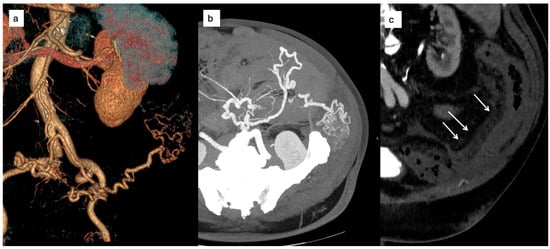

A 71-year-old woman with a medical history of diabetes mellitus, hypertension, and dyslipidemia presented with a two-month history of progressive, non-specific abdominal pain localized to the left lower quadrant. She was initially admitted to the emergency department of another hospital. She denied hematochezia, diarrhea, weight loss, or constitutional symptoms. The physical examination of the abdomen was unremarkable, and there were no clinical signs or symptoms of portal hypertension. Full laboratory tests yielded normal results. An initial contrast-enhanced computed tomography (CT) scan performed at another institution revealed abnormal dilatation of mesenteric vessels with early venous filling, suggestive of a high-flow vascular lesion. The patient was referred to our center for further evaluation. CT angiography confirmed the presence of an inferior mesenteric arteriovenous malformation consistent with a Yakes type IIb lesion, characterized by a compact nidus and aneurysmal dilatation of the draining vein, unknown to the patient (Figure 3).

Figure 3. (a) Finding at CT scan of an IMAVM with the aneurysmal dilation of the venous drainage; (b) DSA: superselective angiography of the AMI highlighting the angioarchitecture of the malformation.

Subsequently, digital subtraction angiography (DSA) was performed via the right femoral artery for definitive characterization and treatment planning.

Superselective catheterization of the feeding branches of the IMA was achieved using a microcatheter. Embolization was performed with a mixture of n-butyl cyanoacrylate (Glubran® 2) and Lipiodol®, resulting in complete exclusion of the nidus. A limited, clinically silent dissection of the IMA was observed at the end of the procedure, without impairment of distal perfusion.

Post-procedurally, the patient was managed conservatively. Antiplatelet therapy with acetylsalicylic acid (100 mg/day) was initiated due to the arterial dissection. No signs of bowel ischemia were observed, and the patient experienced progressive resolution of abdominal pain. Although elective surgical resection had initially been considered, it was deferred in light of clinical improvement.

At 12-month follow-up, CT angiography demonstrated persistent occlusion of the nidus with preserved colonic perfusion and a patent, remodeled IMA (Figure 4). The patient remained asymptomatic and free from abdominal pain.

Figure 4. (a) selective microcatheterization of the AMI and embolization, (b) complete occlusion of the nidus with residual dissection of the AMI; (c) one year CT: persistent occlusion of the nidus with opacified dissecting AMI.